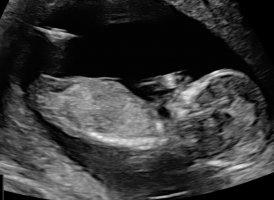

Det var i slik vinkel som bilde nr 2 her at min GY også gjetta på jente 12+3Synes ikke så godt her.. målt til 12+2 men gyn hadde en anelse ved bilde 2 der![]()

hu såg aldri etter "nub".